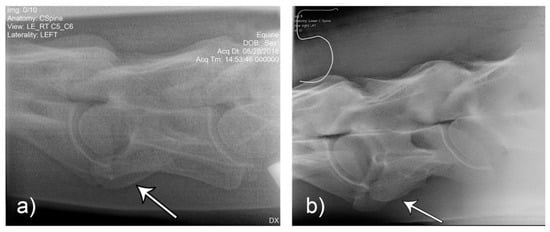

Figure 10. Laterolateral images F1 (a) and M2 (b) represent the malformation presentations of ECCMV: Unilateral (F1) and bilateral with (variable) bilateral transposition onto C7 (M2). Arrows indicate the abnormal line of the lamina in the absence of the caudal lamina of the transverse process.

Comparison of the unilateral and bilateral presentation variations of C6 was possible on the laterolateral views (Figure 10).

Two common operator and reviewer errors are identification of a false bilateral morphologic variation of C6 when actually imaging the normal C5 vertebrae. Conversely, diagnosing the bilaterally absent ventral laminae on C6 as normal is another common mistake (Figure 10c). It should be noted that the caudal ventral tubercles of C6 have separate centers of ossification that may be misdiagnosed as fractures [7]. Asymmetry of the articular process joints in the cervical spine may make true laterolateral image capture difficult [7]. The laterolateral images of C6, along with the dorsal to ventral oblique images, are key to interpreting the symmetry, length, and shape of the lamina (Figure 4c). Field radiographs make the assessment of transposition on to C7 difficult in some cases. The transposition may be visible less commonly on the oblique views (Figure 9b) depending on the shape and position of the transposition [11]. Transposition on to C7 is more commonly seen on the laterolateral views and is usually seen below the transverse processes [11]. In some cases, the transposition may be seen on the oblique view (Figure 9b). Some three-dimensional alterations are so severe that misinterpretation of the morphology on C7 can occur (Figure 8c). This highlights the need for more detailed diagnostic assessment in these cases. Spinal cord compression by an asymmetrical canal, articular process periarticular bone formation and extent of intravertebral foramina compression cannot be assessed by radiography alone [10]. The study of the prepared vertebra in three dimensions is key to understanding the potential alterations in regional biomechanics.